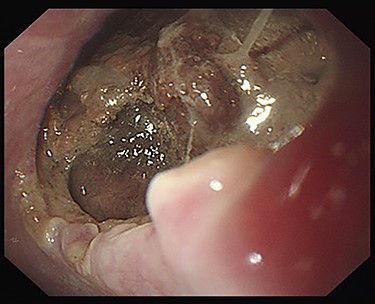

Seven days after TEVAR, the patient developed fever, and a CT scan showed bilateral iliopsoas abscesses and gas images inside the aneurysm (Fig. 2). We decided to perform upper gastrointestinal endoscopy and CT-guided drainage for abscesses. Endoscopy showed perforation of the esophageal wall and accumulation of necrotic tissue (Fig. 3).

CT seven days after TEVAR. Arrow shows gas images inside the aortic aneurysm.

Esophagoscopy revealing an aortoesophageal fistula covered by necrotic tissue.